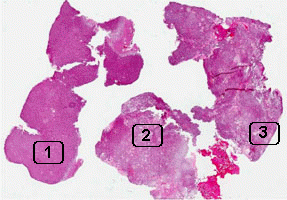

Online Slide/Full Screen/Open with ImageScope